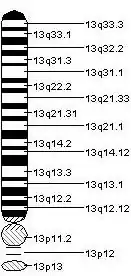

Gene

The 5-HT2A receptors is coded by the HTR2A gene. In humans the gene is located on chromosome 13. The gene has previously been called just HTR2 until the description of two related genes HTR2B and HTR2C. Several interesting polymorphisms have been identified for HTR2A: A-1438G (rs6311), C102T (rs6313), and His452Tyr (rs6314). Many more polymorphisms exist for the gene. A 2006 paper listed 255.[15][16]

Human HTR2A gene is thought to consist of 3 introns and 4 exons and to overlap with human gene HTR2A-AS1 which consists of 18 exons.[18] There are over 200 organisms that have orthologs with the human HTR2A. Currently, the best documented orthologs for HTR2A gene are the mouse,[19] and zebrafish.[20] There are 8 paralogs for the HTR2A gene. The HTR2A gene is known to interact and activate G-protein genes such as GNA14, GNAI1, GNAI3, GNAQ, and GNAZ.[21] These interactions are critical for cell signaling[22][23] and homeostasis[24] in many organisms.[25]

In human brain tissue, regulation of HTR2A varies depending on the region:[18] frontal cortex, amygdala, thalamus, brain stem and cerebellum. In a paper from 2016, they found that HTR2A undergoes a variety of different splicing events, including utilization of alternative splice acceptor sites, exon skipping, rare exon usage, and intron retention.[18]